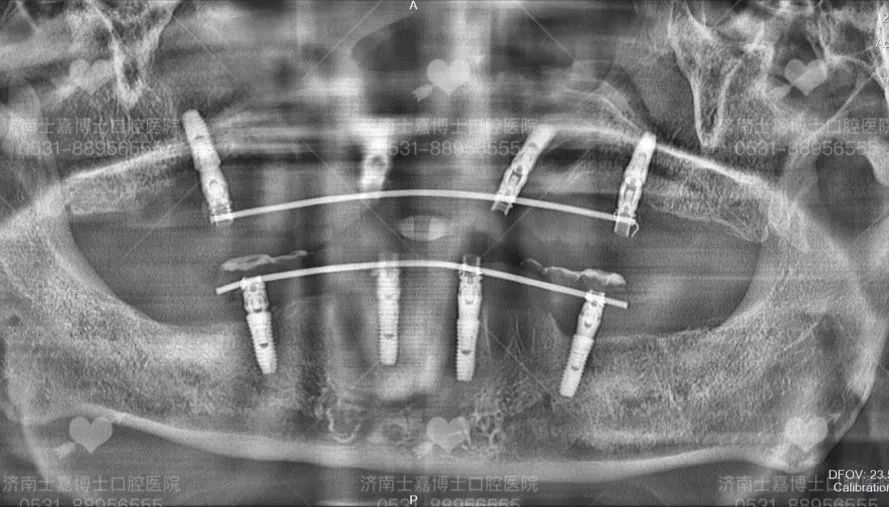

医生技术好 · 种牙不受罪 · 牙齿用到老 种植牙的成功与长久使用,与医生的医疗技术和水平及医院的设备有着直接的关系。那么由谁种,是种植牙成功的关键! 下面将从几个方面来看,如何选择一个好的种植医生。 一、看学历/资质 学历背景很重要,尽量选择口腔医学院校毕业的医学生,这些在专业口腔医学院校接受的培训和掌握的技术更规范和先进,水平较高的种植医生一般都是硕士、博士级别。 二、看进修背景 种植科医生会不断进修,一般选择口腔专科医院或是大型综合三甲医院口腔科或是国外的牙科学院进行进修学习 三、看种植技术,尤其是复杂种植完成质量 医生技术好,种植后就极少出现种植体与骨之间愈合不好而导致的牙松动、脱落等,越能把握种植牙长期效果,尤其是针对复杂牙种植后的完成质量,更是“一牙见分晓” 种植过程中,技术好的医生对种植体植入到牙槽骨的把握力度更好,对于基台穿龈的准确度就越高,为保证种植牙长久的使用打下良好基础 尤其是中老年人普遍面临着半口/全口缺牙、长期缺牙、牙槽骨萎缩吸收等难题,传统种植技术对老人身体损伤较大,导致无法实现种牙。而娴熟掌握先进技术的种植医生,能够做到少植骨或不植骨,更能保证种植后的效果和质量 四、看种植案例数量 种植牙是一项精细的医学手工技术,一般来说,临床经验越丰富,医生技术就会越好,种了100颗牙与种了10000颗牙的医生,在技术经验是有很大差别的,针对牙齿种植,所种植的数量越多,就能更好的帮患者患者减少种植过程中的手术痛苦、保证种植牙的长久使用 所以,选择医生一般都会选择种植经验丰富,这在很大程度上决定了种植牙后期的使用效果以及使用寿命 士嘉博士口腔医院舒适化种植团队 从种植体设计、生产,到医生把种植体植入牙槽骨,再到完成种植后患者的个人生活习惯,每一个环节、每一个细节都会影响种植体表面骨改建的动态平衡,继而影响种植成功还是失败。 因此,选择一个有经验有技术的种植医生尤为重要。 张士杰,山东大学口腔医学院博士研究生导师、教授、博士后,山东大学齐鲁医院口腔正畸科主任、主任医师。中华医学会口腔正畸专业委员会委员,中华医学会整形美容牙颌颜面美容分会常委,世界正畸联盟WFO会员。曾赴日本东京医科齿科大学、美国康州大学牙医学院、美国哈佛大学种植研修中心访问交流。发表学术论文四十余篇,其中被SCI收录十五篇,获山东省科技进步三等奖一项。承担国家自然科学基金、山东省自然科学基金、山东省科技攻关、山东大学自主创新、山东省重大专项等多项科研项目。口腔临床技能全面,以先进技术为基础、结合国外口腔诊疗服务理念,通过口腔正畸、种植修复、牙周治疗、牙齿美容等全面为患者提供适合的治疗方案,注重人文关怀。 擅长:成人及青少年各类牙齿畸形的矫正治疗,隐形矫正(山东省首批美国隐适美隐形矫正认证专家),在诊疗牙齿前突、开唇露齿、地包天、唇腭裂等正畸正颌联合手术治疗方面尤其突出,尤其擅长复杂牙列缺失的种植修复和咬合重建治疗。 高万郝,主治医师,山东大学口腔医学硕士,北京大学口腔医学院进修 擅长:各类牙齿种植、智齿拔除等口腔手术,熟练掌握多套国际先进的种植系统有多年口腔种植临床经验,尤其擅长复杂病例的咬合重建 病例分享一:77岁老人全口种植 父亲节当天,77岁的老人来士嘉博士口腔全口种植,老人得过脑梗、有心衰,本不想做牙齿上的治疗,在儿子坚持下做了种植,当天做到即刻拔牙即刻修复即刻全口种植,拔牙后吃上肉包子,由衷的感叹:香! 病例分享二:80岁奶奶上半口种植初体验 奶奶说“效果很好,牙齿很漂亮,一点都不痛!” 五、看选择的种植机构 口腔种植学,不仅是独立的学科,且涉及口腔颌面外科学、修复学、牙周病学、材料学、生物力学、影像学等口腔各学科领域。 先进的种植仪器 士嘉博士口腔医院坚持设备与国际同步,倡导舒适化的诊疗理念 我们引进了德国卡瓦3D数字化影像设备、德国3D瓷睿刻数字化牙椅旁修复系统、德国3D打印数字化种植导板系统、瑞士美国德国韩国等世界品牌种植系统等 能够提供当天就诊、当天戴牙,大大缩短了患者的等待时间。个性化服务更好,义齿生产质量更精密,还能快速解决临床戴牙所遇到的问题,更舒适、效率更高,客户满意度大大提高